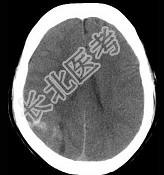

- 单项选择题男,37岁, 头痛、头晕1年余,加重3天, CT检查如图所示,最可能的诊断是 ( )

A、脑血管畸形并出血

B、转移瘤并出血

C、颅内动脉瘤

D、脑出血

E、脑膜瘤并出血